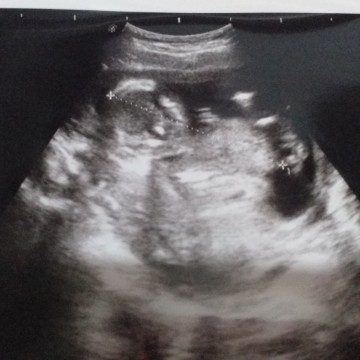

USG YG KE 2

Sehat" di perut mama ya nak . 13wekk?♥️♥️